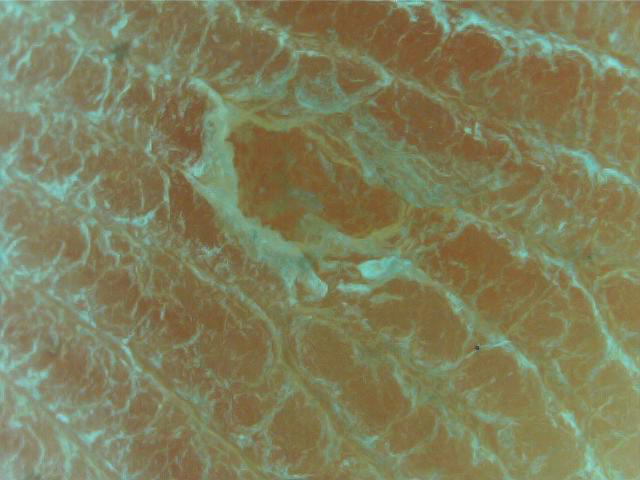

관리 전후사진

발바닥 티눈의 원인분석 및 발바닥 굳은살 관리전 상태

1. 발바닥에 티눈과 굳은살이 1년전 발생한 상태입니다.

2. 발바닥에 티눈과 굳은살을 뜯어내는 습관이 있으셨습니다 뜯을때 출혈이 있었습니다.

3. 발바닥 티눈과 굳은살 때문에 티눈밴드를 사용했으나 효과가 전혀 없었습니다.

4. 병원 피부과에서 발바닥 티눈 통증과 굳은살로 인하여 1달전에 레이져수술을 하고 재발이 되어 분당푸스올에 방문해주셨습니다.